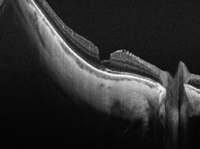

3 fueron los primeros en describir las alteraciones de la retina desprendida: engrosamiento retiniano, separación de las capas intraretinianas y ondulaciones de la retina externa (

Figura 1 y

Figura 2). Por último, Yetik

Figura 1. Desprendimiento de retina crónico. Se observan separaciones en las capas intraretinianas (Topcon SS-OCT DR-1).

Figura 2. Desprendimiento de retina agudo. Se observan ondulaciones de la retina externa (OLU) (Topcon SS-OCT DR-1).